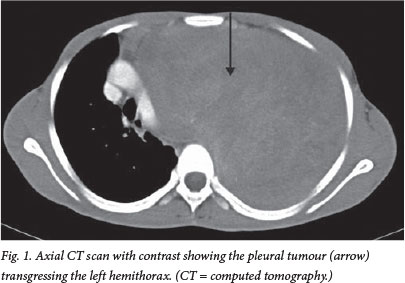

The chest radiograph on admission suggested pleural space occupation with contralateral mediastinal shift. A computed tomography (CT) scan of the chest and mediastinum confirmed a pleural mass of about 25 cm χ 17 cm with mediastinal shift and compression of the underlying left lung (Fig. 1). A core biopsy of the pleural mass was suggestive of a spindle cell tumour, but the differential diagnosis varied widely and included fibromatosis.